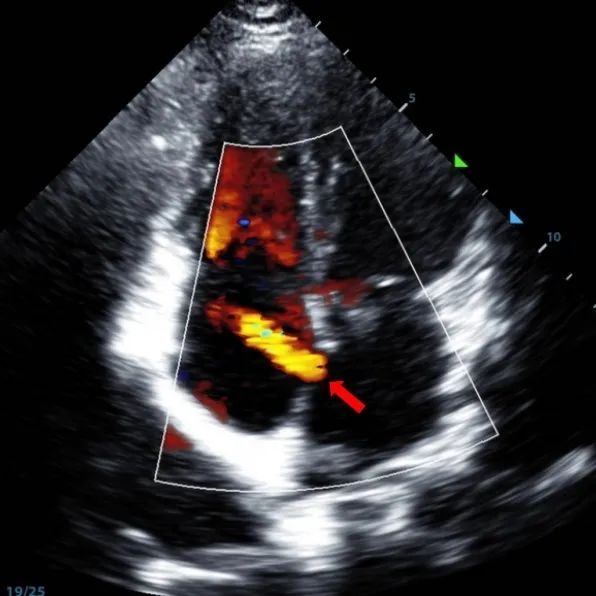

Um homem de 9 anos com ASD secundum (7,5-7,9mm) foi tratado usando um oclusor MemoSorb BDASD-I 12mm e sistema de entrega 12F. Não foram observadas complicações ou comorbidades pré-procedimento.

Serial echocardiographic follow-ups showed stable device position and favorable cardiac remodeling. Gradual degradation confirmed the occluder's long-term safety and efficacy.